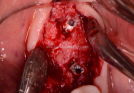

Clinical Cases

• Case1

• Case2

• Case3

• Case4

• Case5

• Case6

• Case7

• Case8

• Case9

• Case10